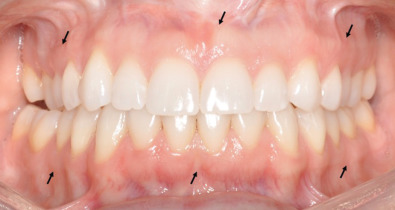

An accurate maxillofacial examination is only possible following adequate exposure, which includes cleaning the patient’s face and wound. Given the vascularity of the maxillofacial region, blood and debris from even minor soft tissue lacerations can misrepresent the severity of injury. Proper cleaning and examination of wounds may require sedation or general anesthesia to ensure patient comfort. A standard set of photographs should be obtained of patients sustaining facial trauma ( Fig. 1.18.5 ), including anterior, lateral, submental, intraoral, and wound photographs. These photos provide a baseline examination for medicolegal purposes, allow for a visual tool to describe treatment to the patient, and aid the clinician in forming the definitive treatment plan. This chapter will focus on the examination of the oral cavity and mandibular function.